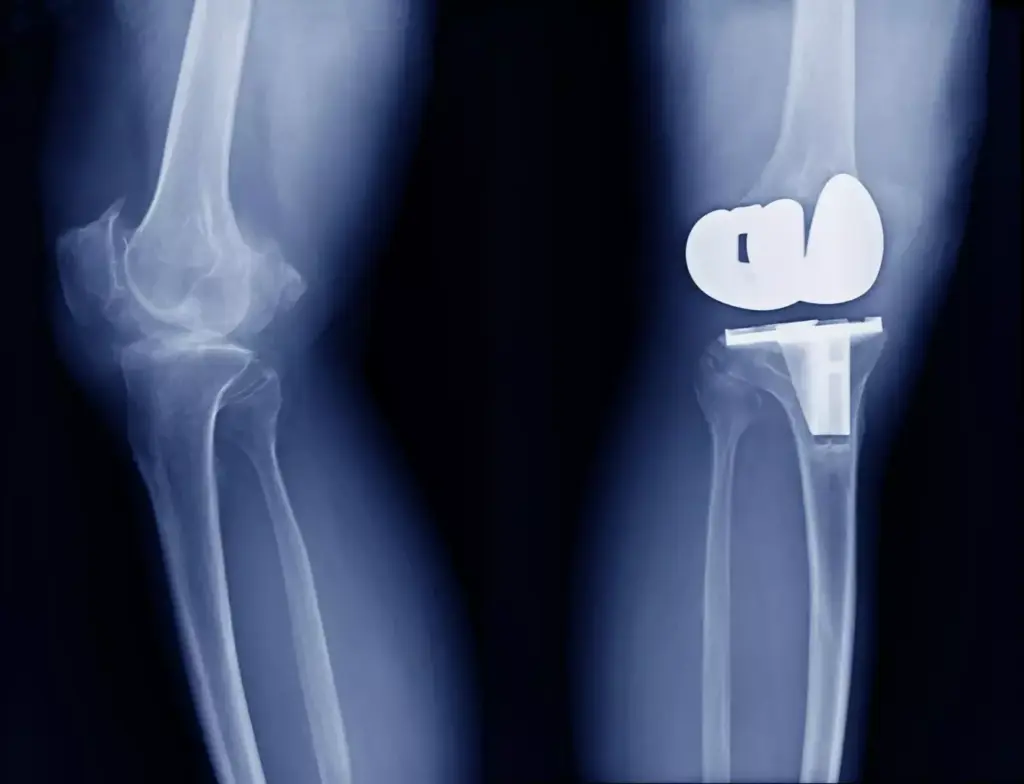

To diagnose aseptic loosening, doctors use a few methods. They look at how the knee feels, take X-rays or CT scans, and sometimes do bone scans. This helps them see how loose the implant is.

It’s key to catch aseptic loosening early. This helps avoid more problems and keeps the ceramic knee replacement working well. Regular check-ups with your doctor are important. They help make sure the implant is doing its job right.